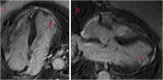

"Cases of SCMR" is a case series on the SCMR website (https://www.scmr.org) for the purpose of education. The cases reflect the clinical presentation, and the use of cardiovascular magnetic resonance (CMR) in the diagnosis and management of cardiovascular disease. The 2022 digital collection of cases are presented in this manuscript.

Keywords: Arrhythmogenic cardiomyopathy; COVID-19; Cardio-oncology; Congenital Heart disease; Coronary artery aneurysm; Hydatid disease; Hypertrophic cardiomyopathy; Metastatic disease; Myocardial. infarction; Myocarditis; Takotsubo; Vaccine associated myocarditis; Viability.